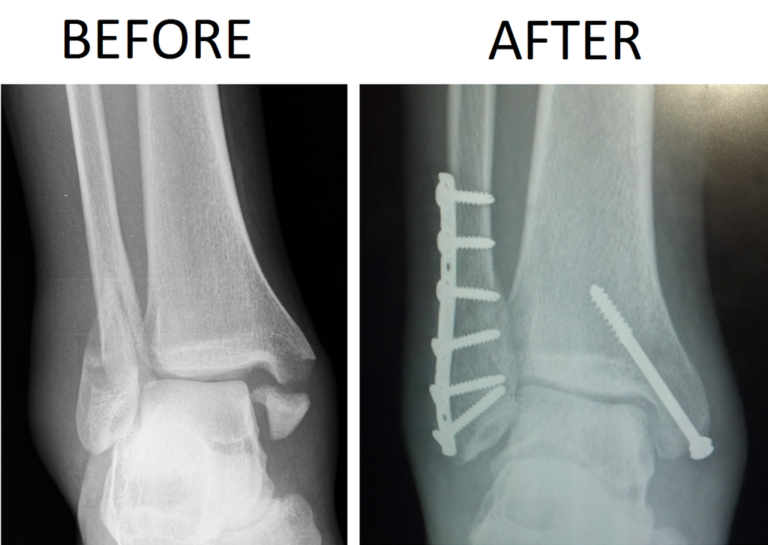

Ankle Fracture repair Broken Ankle Doctor Sugar Land, Pearland, Houston, TX Sports Fracture Ankle The stresses, direct blows and twisting. You may be at higher risk of a broken ankle if you: Ankle fractures are common injuries that could result from a trivial twisting injury in old frail patients up to high energy trauma in a young population. A stress fracture is a small crack in a bone, or severe bruising within a bone.. Sports Fracture Ankle.

Ankle Fracture Surgery Orthopedics Sports Medicine Sports Fracture Ankle A stress fracture is a small crack in a bone, or severe bruising within a bone. Ankle fractures are common injuries that could result from a trivial twisting injury in old frail patients up to high energy trauma in a young population. The stresses, direct blows and twisting. Most stress fractures are caused by overuse and repetitive activity, and are. Sports Fracture Ankle.